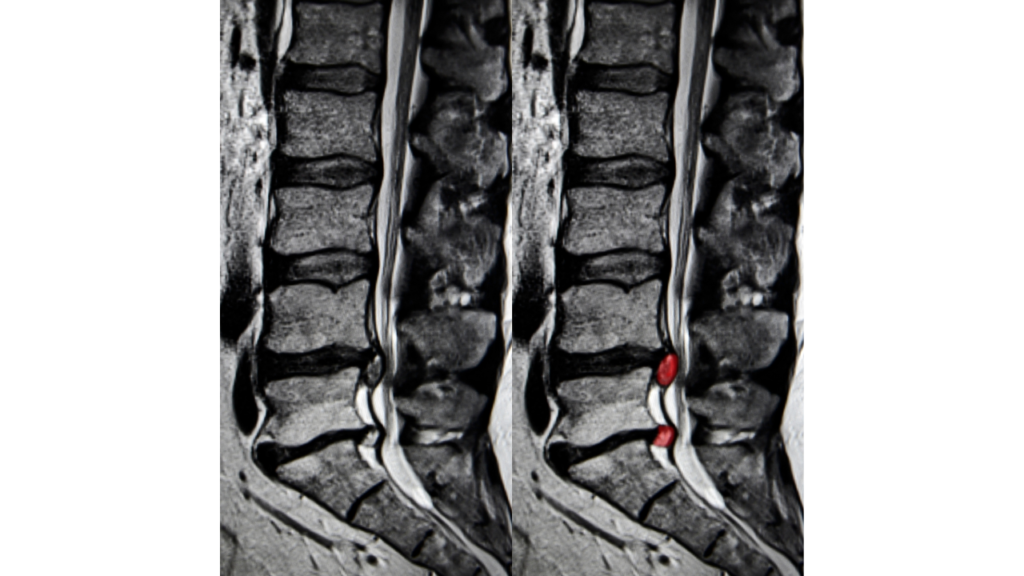

- 腰部脊柱管狭窄症

- 腰椎椎間板ヘルニア